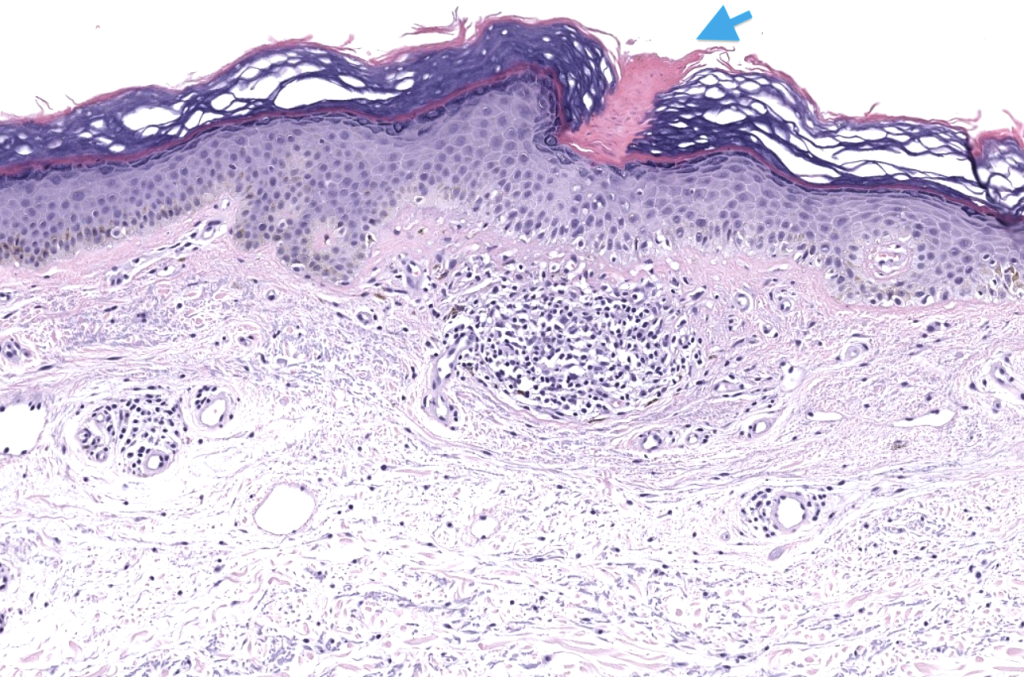

- Grupo heterogéneo de trastornos de queratinización caracterizados clínicamente por placas/pápulas anulares con borde hiperqueratósico y atrofia central, e histológicamente por la lamela cornoide (cornoid lamella). Vargas-Mora 2020, Kostopoulos-Kanitakis 2025

- Biopsia: punch/incisional del borde (ideal 4–6 mm incluyendo cresta). Vargas-Mora 2020